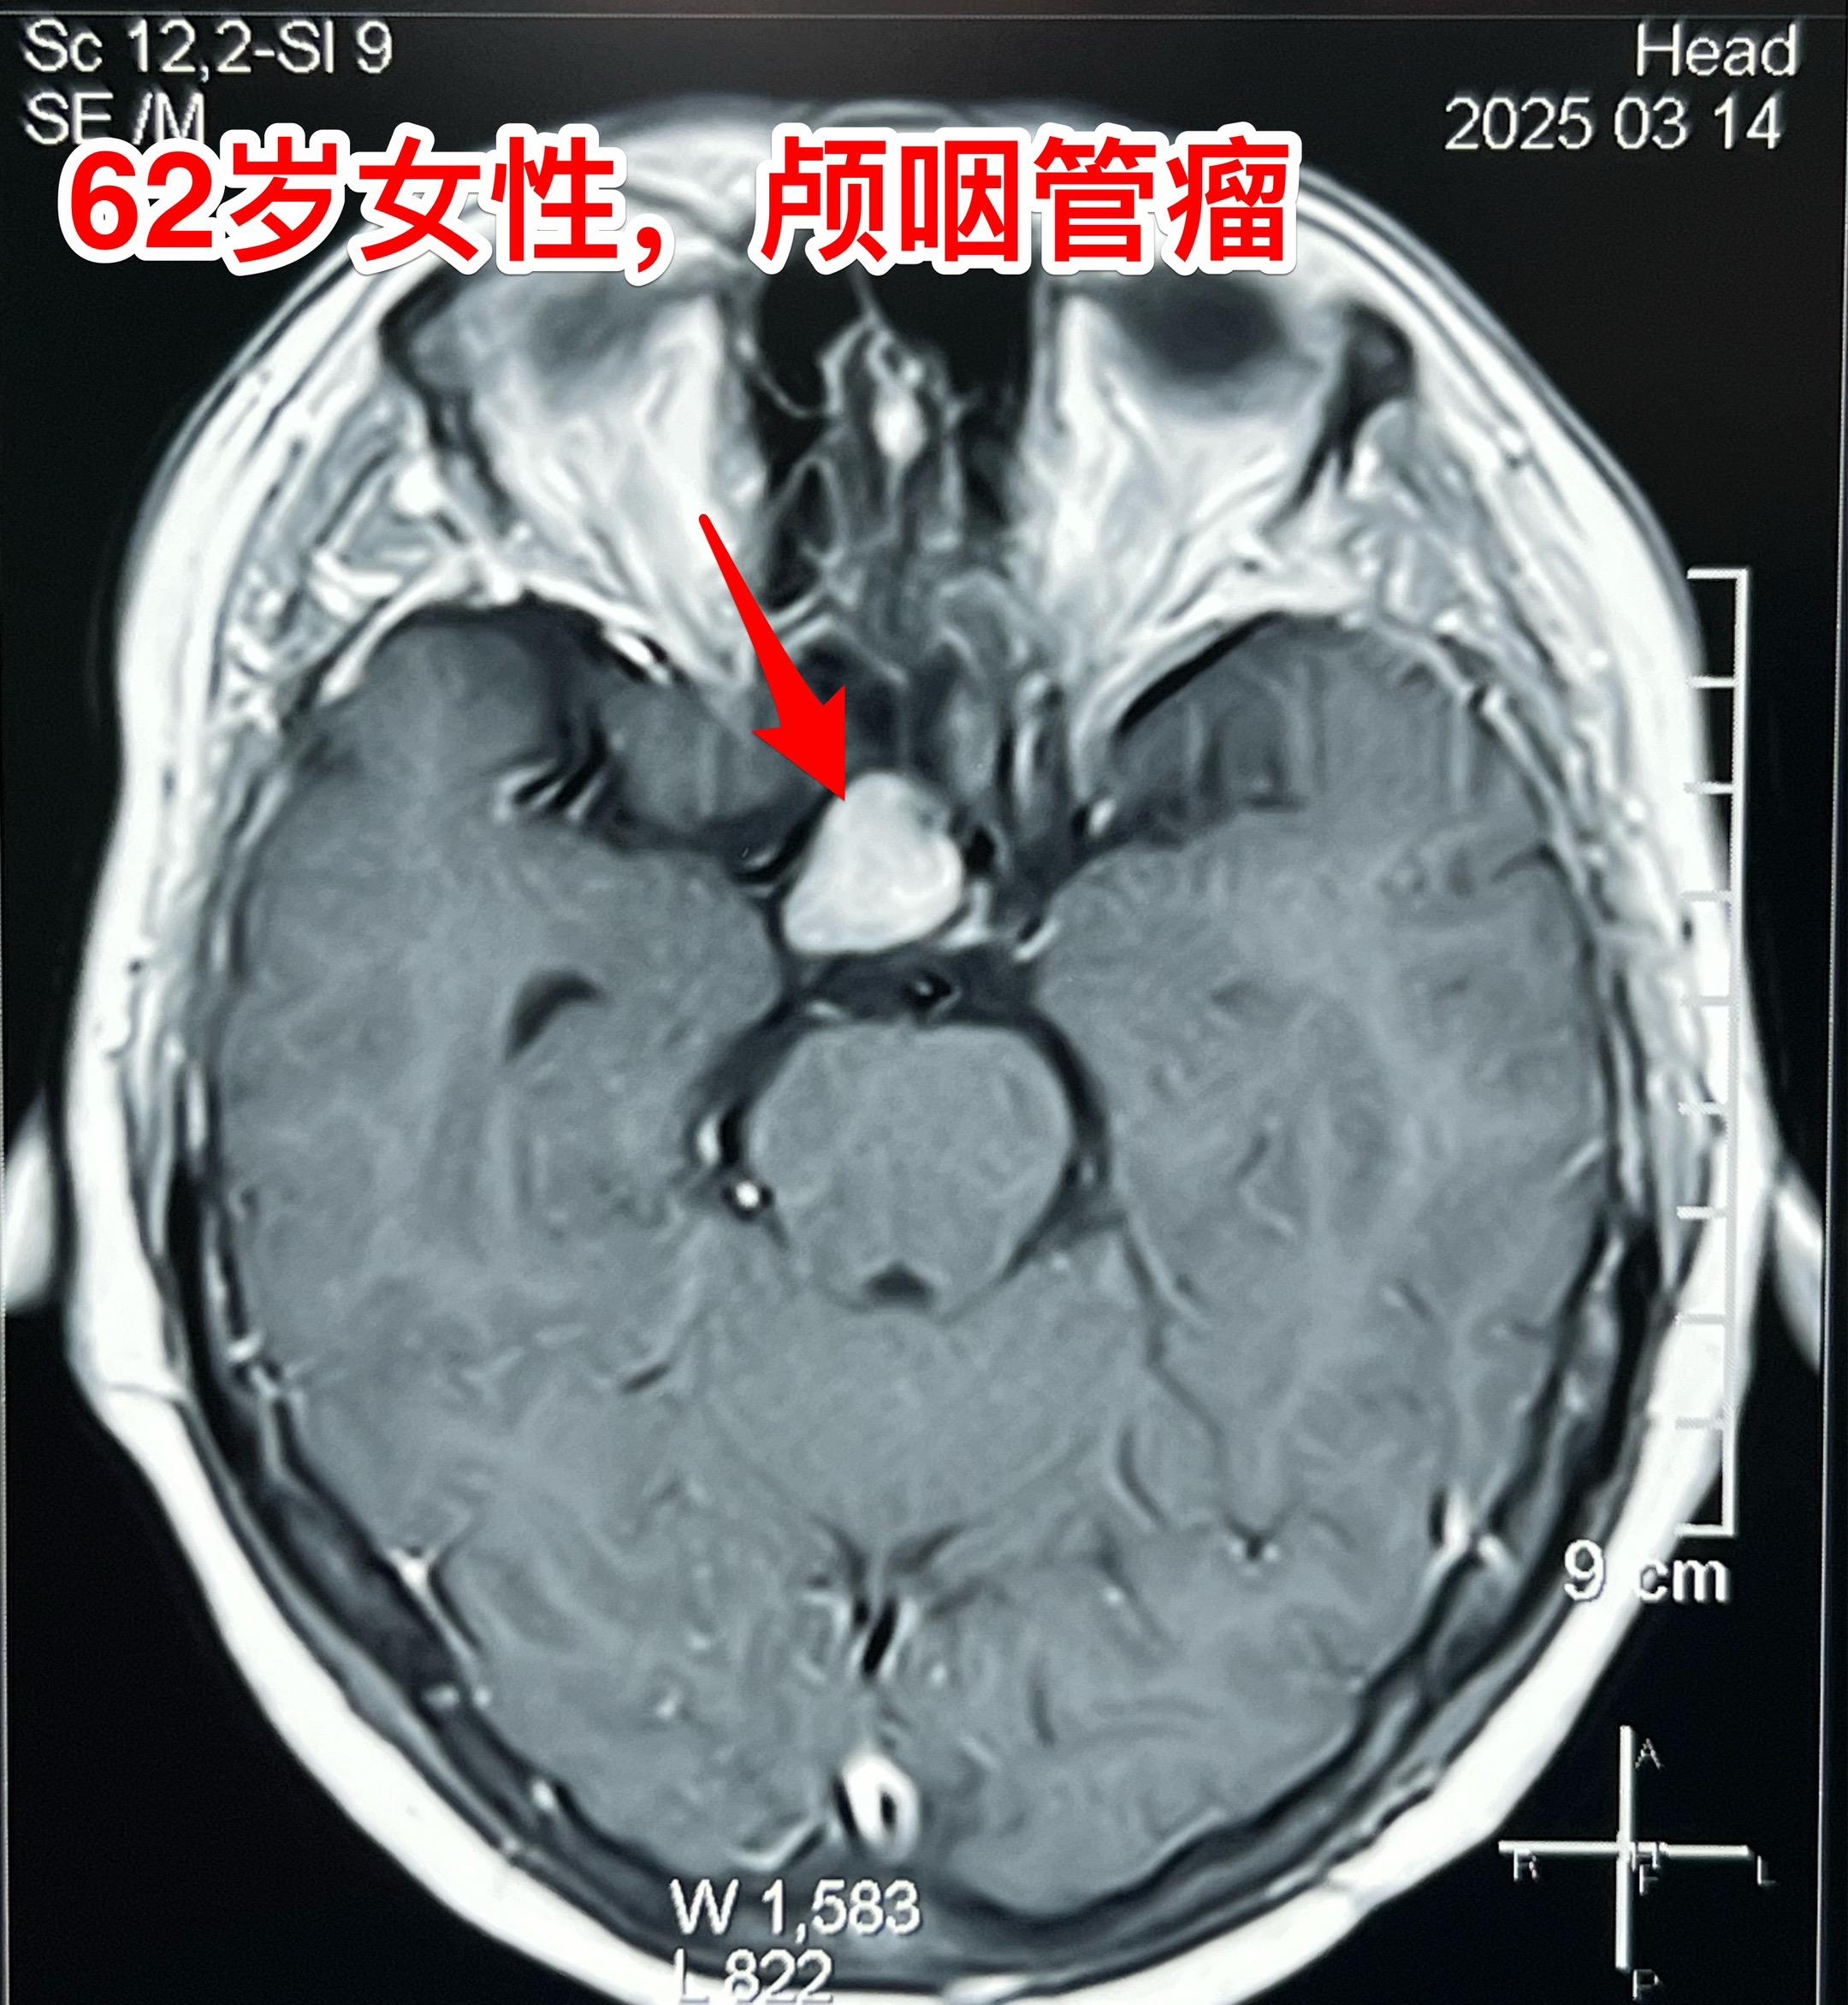

经翼点入路切除颅咽管瘤-不能忘记的入路 经翼点入路切除颅咽管瘤,曾经是广泛使用的一种入路,当然有其优点。近十几年使用这个入路切除颅咽管瘤的机会大大减少了。 对于比较小的鞍上型颅咽管瘤或者自中线偏向侧裂池方向生长的颅咽管瘤,这个入路是很适合的。 3月21日为62岁女性病人切除颅咽管瘤,采用的就是经翼点入路。肿瘤得到完全切除,垂体柄得到保护[强]